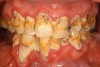

Lewis highlighted that generalized cervical buccal heavily stained carious lesions can be pathognomonic in both methadone and heroin addicts, similar to those who have undergone radiotherapy of the head and neck and those who take multiple xerostomic medications.13 Sheedy compared the detrimental effect of methadone to the oral cavity and coined the term “Methadone Mouth” to characterize the extreme poor oral health conditions of most long–term MMT individuals, particularly with rapid tooth destruction due to aggressive carious activity (Figure 1).24 Methadone Mouth should not be mistaken, however, with “Meth Mouth” (Figure 2 and Figure 3).

Meth Mouth is a term associated with the use of the elicit drug methamphetamine.40 Although some methadone and methamphetamine users can present with the same oral condition, the later tend to be more often associated with higher gross decay to the extent that the “teeth are in such disrepair that they are unsalvageable and must be extracted.”41

Figure 2  Meth mouth.

Figure 2